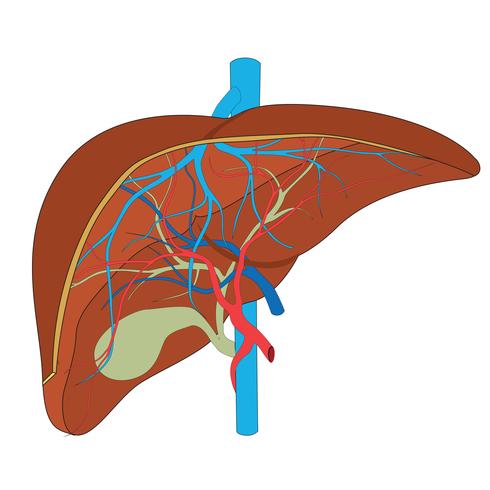

La bifurcación de la vena porta hepática es asimétrica, dando lugar a una rama derecha que parece prolongar el trayecto del tronco principal de la vena porta hepática, y una rama izquierda, de menor tamaño, que se separa en ángulo recto de la rama derecha. Cada una de estas venas, junto con sus ramas de división, está acompañada por una arteria, un conducto biliar y una vaina conectiva que depende de la cápsula fibrosa del hígado. Cada conjunto forma una raíz, siendo las raíces derecha e izquierda las responsables de irrigar las dos partes distintas del hígado: el hígado derecho y el hígado izquierdo.

El hígado derecho está dividido en segmentos anterior y posterior por la fisura portal derecha, mientras que el hígado izquierdo se divide en segmentos medial y lateral por la fisura del ligamento redondo. Además, el lóbulo caudado constituye un segmento autónomo.

Cada segmento presenta territorios terminales denominados sectores hepáticos. Las venas hepáticas ubicadas en las fisuras drenan los segmentos adyacentes hacia la vena cava. El hígado derecho, situado a la derecha de la fisura portal principal y dependiente de la raíz hepática derecha, recibe irrigación de la vena porta hepática derecha, que se divide en:

La vena porta hepática izquierda, con un trayecto de mayor longitud que la derecha, tiene una subdivisión única con dos porciones: